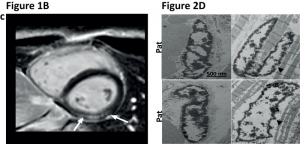

Neue Genmutation entdeckt, die dilatative Kardiomyopathie auslöst2. Mai 2019 Dr. Ruping Chen untersucht am DZHI die Folgen der LEMD2- Mutation im Mausmodell und hat schon nach wenigen Wochen Veränderungen am Herzen, im Sinne einer Kardiomyopathie, entdeckt. Foto: © Daniel Oppelt Ruping Chen vom DZHI Würzburg wurde für ihre Arbeit mit dem Hans Blömer-Young Investigator Award für Klinische Herz-Kreislaufforschung geehrt. Rund 50 Gene wurden bislang als Auslöser für eine dilatative Kardiomyopathie (DCM) gefunden. Mit der Entdeckung des LEMD2-Gens haben die Kardiogenetikerin Prof. Brenda Gerull und ihre wissenschaftliche Mitarbeiterin Dr. Ruping Chen vom Deutschen Zentrum für Herzinsuffizienz Würzburg (DZHI) das Spektrum der genetischen Ursachen für die Herzschwäche erweitert. Die Mutation im Kernmembranprotein LEMD2 verursacht nicht nur Herzrhythmusstörungen, die im plötzlichen Herztod münden können, sowie eine Herzschwäche, sie geht auch mit einem Katarakt im frühen Kindesalter einher. Diese Linsentrübung ist üblicherweise eine Erkrankung des hohen Lebensalters. Über die Entdeckung des veränderten „Alterungsgens“ und dessen molekulare Folgen haben die Forscher einen wertvollen Beitrag zum weiteren Verständnis genetischer Kardiomyopathien geleistet, dem jetzt ein Artikel im „Journal of the American College of Cardiology (JACC): Basic To Translational Science“ gewidmet ist. Zeitgleich wurde Ruping Chen gerade für ihre weiterführenden Untersuchungen zur Rolle des Kernmembranproteins im Modellsystem beim DGK-Kongress in Mannheim mit dem 2. Platz beim Hans Blömer-Young Investigator Award für Klinische Herz-Kreislaufforschung ausgezeichnet. „Es ist schon etwas länger bekannt, dass LEMD2 eine Linsentrübung im frühen Kindesalter auslöst, die landläufig als grauer Star bekannt ist. Wir haben nun herausgefunden, dass diese Mutation im LEMD2 neben dem Katarakt auch eine schwere Form der Kardiomyopathie verursacht, ähnlich der Mutationen im sogenannten Lamin-Gen. Interessanterweise können beide Proteine im veränderten Zustand auch zu Frühalterungskrankheiten führen, zu denen die Progerie gehört“, berichtet Gerull, Leiterin des Departments Kardiovaskuläre Genetik am DZHI. Das linke Bild zeigt ein MRT-Bild des Herzens. Die weißen Pfeile weisen auf Narben in der Wand der linken Herzkammer hin, die durch den Gendefekt im LEMD2 entstehen können. Rechts elektronenmikroskopische Aufnahmen von veränderten Zellkernen im betroffenen Herzmuskelgewebe. Abbildungen adaptiert aus © „Journal of the American College of Cardiology (JACC): Basic To Translational Science“. Quelle: Universitätsklinikum Würzburg „Patienten mit dem Gendefekt bilden Narben im Herzmuskelgewebe aus, die dann zu den gefürchteten Herzrhythmusstörungen schon bei jungen Erwachsenen führen können“, erklärt die Forscherin und zeigt dabei auf die hellen Stellen eines MRT-Bildes vom Herzen. Zur Erläuterung der Veränderungen auf zellulärer Ebene greift sie zu einer elektronenmikroskopischen Aufnahme mit bizarr aussehenden Zellkernen: „Sowohl das Herzmuskelgewebe von Betroffenen als auch deren Hautzellen weisen veränderte Zellkerne auf, wobei das in der Peripherie des Zellkerns liegende Heterochromatin stark kondensiert und verklumpt erscheint.“ Weitere Untersuchungen an den Fibroblasten haben gezeigt, dass die Zellen schneller altern, der Zellzyklus verlangsamt abläuft und die Profileration eingeschränkt ist, sich also die Zellen langsamer teilen. Die Funktion des humanen LEMD2 Proteins, das im Zellkern eine wichtige Rolle zu spielen scheint, ist noch nicht gut untersucht, weist aber Homologien zu der seit langem bekannten Gruppe anderer veränderter Kernmembranproteine auf, die zu Laminopathien führen. Obwohl an Laminopathien schon länger geforscht wird, sind die komplexen Mechanismen immer noch nicht vollständig verstanden. Eine Fokussierung auf das neu entdeckte LEMD2 könnte das Puzzle vervollständigen und dabei helfen, die Mechanismen, die zu dieser speziellen Form der arrhythmischen Kardiomyopathie führen, zu verstehen und entsprechende therapeutische Ansätze im Gesamtkomplex dieser Proteine zu finden. Chen, seit zwei Jahren Postdoc im Department Kardiovaskuläre Genetik und spezialisiert auf Alterungsforschung, hat bereits einen wichtigen Schritt gemacht, und erste Einblicke in die Mechanismen der neuen Genmutation beim Menschen als auch bei Mäusen bekommen. Mit der CRISPR/Cas9-Technologie wurde die humane Mutation in ein Mausmodell eingebracht und schon nach wenigen Wochen hat die Chen Veränderungen am Herzen, im Sinne einer Kardiomyopathie, entdeckt. Ihre Arbeit wurde beim Kongress der Deutschen Gesellschaft für Kardiologie – Herz-Kreislaufforschung (DGK) in Mannheim Ende April 2019 mit dem 2. Platz beim Hans-Blömer-Young Investigator Award für Klinische Herz-Kreislaufforschung ausgezeichnet. Die Wissenschaftlerin und Mutter eines sechs Monate alten Sohnes freut sich sehr über diese Ehrung, konzentriert sich aber schon auf die nächsten Schritte: „Wir wissen jetzt, dass die Mutation verschiedene Phänotypen hervorruft, sowohl beim Menschen als auch bei Mäusen. Nun gilt es, die molekularen Mechanismen der arrhythmischen Kardiomyopathie zu charakterisieren, die eine LEMD2-Mutation verursacht. Ein Hinweis könnte oxidativer Stress sein. Dazu werden wir mit unseren Kollegen im Department Translationale Forschung am DZHI mitochondriale Messungen durchführen.“ *Publikation: Nelly Abdelfatah, Ruping Chen, Henry J. Duff, Colette M. Seifer, Ilan Buffo, Cathleen Huculak, Stephanie Clarke, Robin Clegg, Davinder S. Jassal, Paul M.K. Gordon, Carole Ober, Care4Rare Canada Consortium, Patrick Frosk and Brenda Gerull. Characterization of a Unique Form of Arrhythmic Cardiomyopathy Caused by Recessive Mutation in LEMD2. JACC: Basic to Translational Science 2019;4(2):204-221. DOI: 10.1016/j.jacbts.2018.12.001 http://basictranslational.onlinejacc.org/content/4/2/204